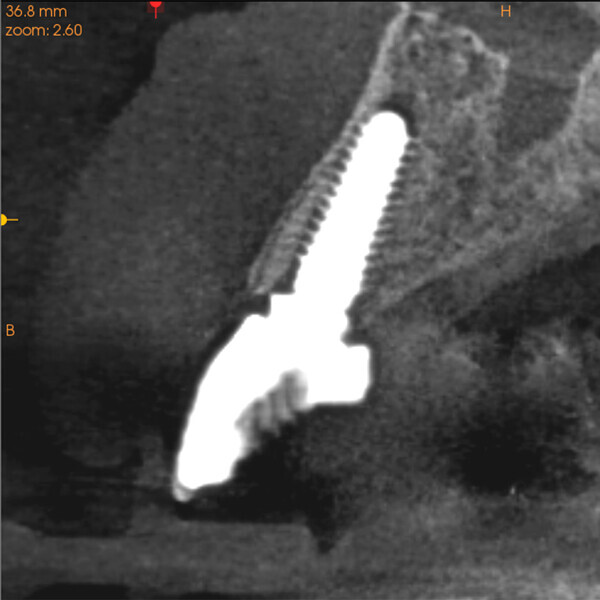

Fig. 14a:

The CBCT cross-sectional image revealed a favourable pre-op condition for a PET procedure.

Fig. 14b: Using the native Carestream 3D Imaging Software,

a simulated implant (red outline) and abutment projection (yellow outline) was positioned within the available bone to avoid the root fragment.